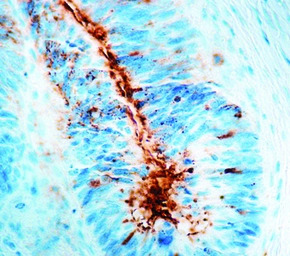

IHC-P analysis of human breast carcinoma tissue using GTX20691 TAG72 antibody [B72.3].